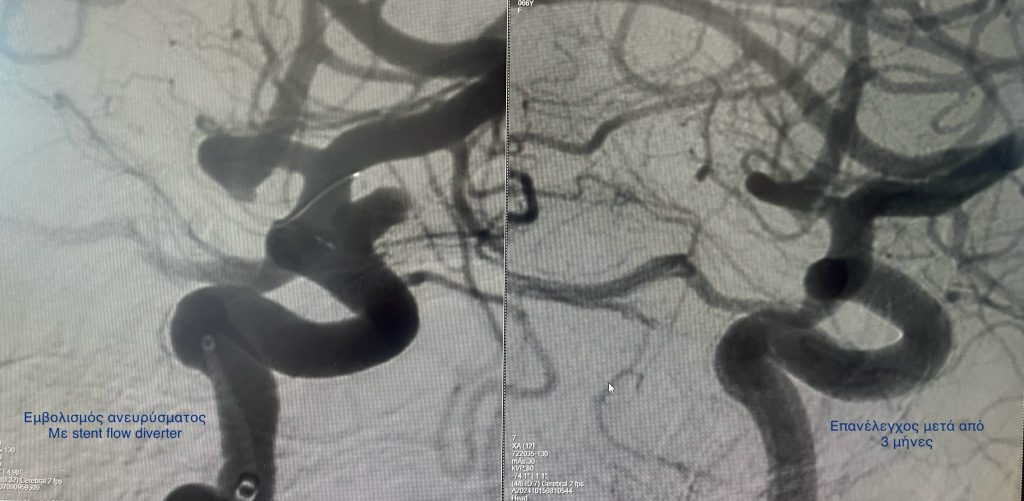

Eμβολισμός ανευρύσματος έσω καρωτίδας με την τεχνική της τροποποίησης της ροής (stent flow diverter)

Και η ενδαγγειακή προσεγγίση. Κατά την προσέγγιση αυτή, πλοηγούμε τα υλικά μέσα από τις αρτηρίες και τοποθετούμε μέσα στο ανεύρυσμα μεταλλικά σπειράματα (coils) μόνα ή σε συνδυασμό με ενδοπρόθεση (stent) ή τοποθετούμε ειδική κατηγορία ενδοπρόθεσης (stent) τροποιητή της ροής στην αρτηρία που φέρει το ανεύρυσμα.